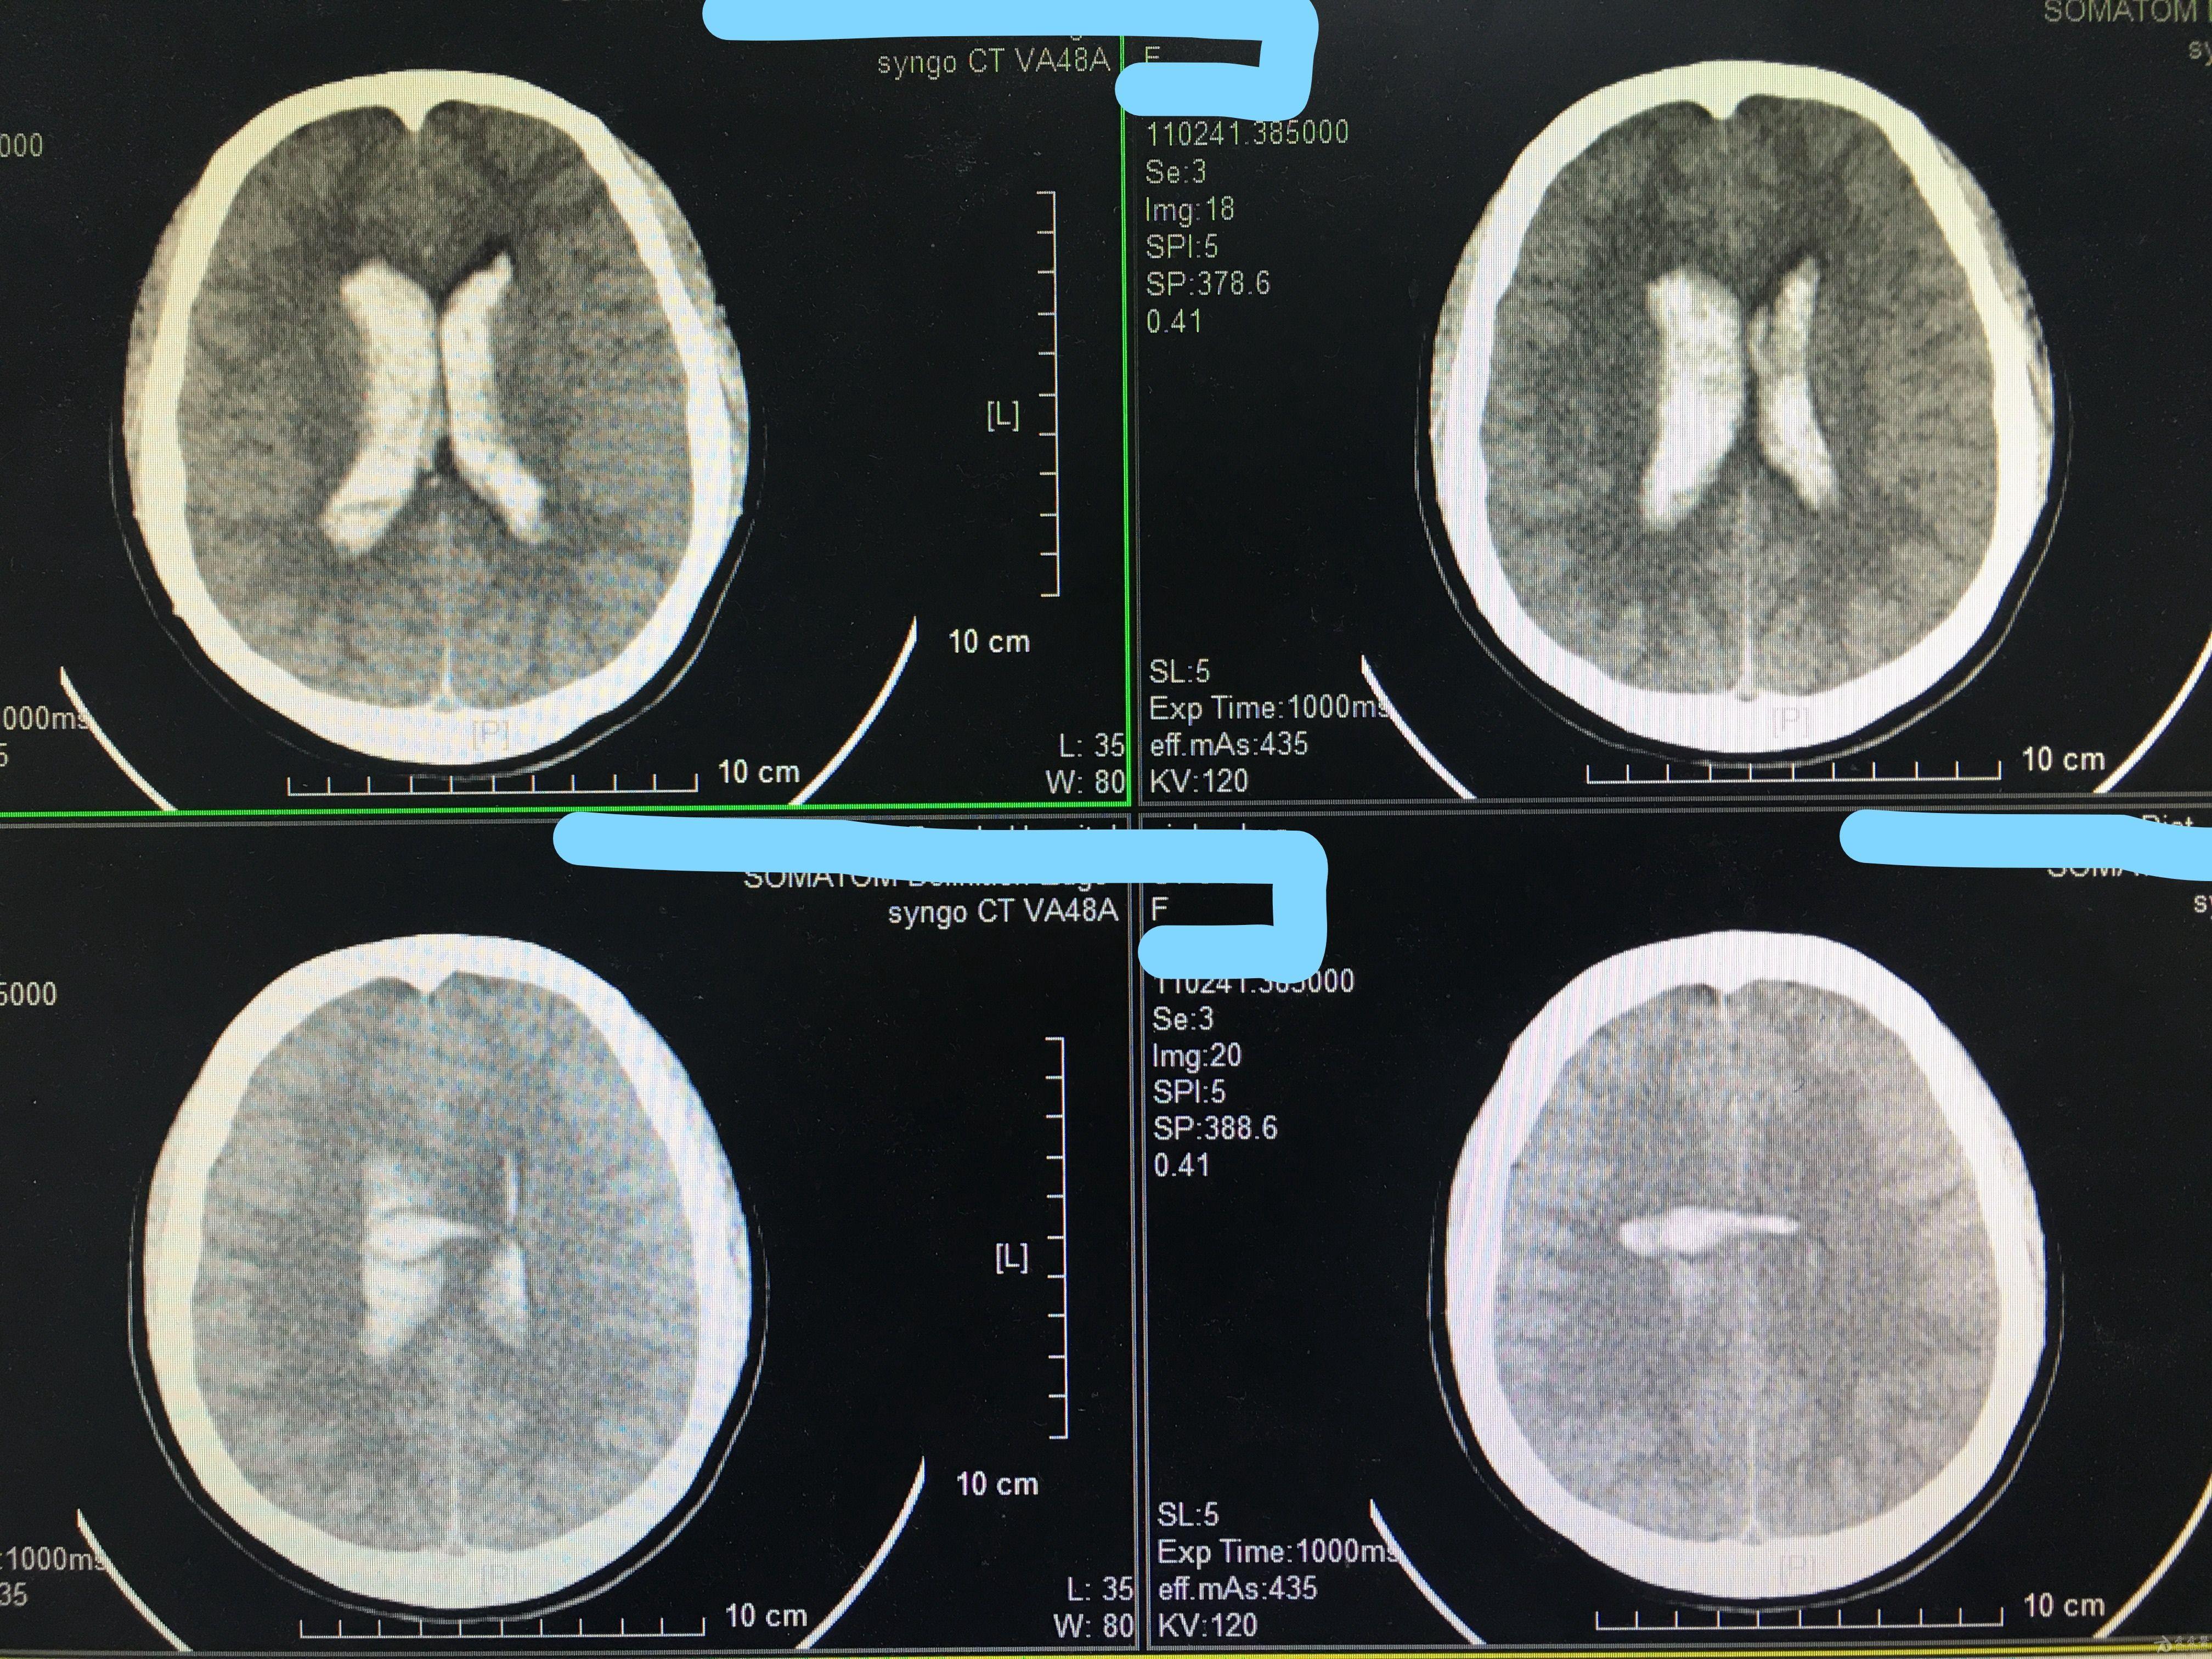

脑室铸型,开颅还是放管?(原创) - 神经外科专业讨论版 - 爱爱医医学论

图片尺寸4032x3024